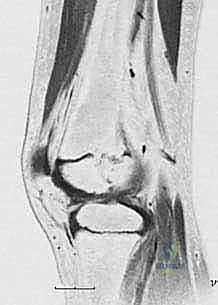

2. التصوير بالرنين المغناطيسي (MRI)

هو المعيار الذهبي (Gold Standard) اليوم. الرنين المغناطيسي يوفر رؤية مباشرة لغضروف صفيحة النمو (الذي لا يظهر في الأشعة السينية). من خلال الـ MRI، يستطيع الدكتور هطيف رسم خريطة دقيقة (Mapping) للعائق العظمي: أين يقع بالضبط؟ وما هي مساحته بالنسبة للمساحة الكلية لصفيحة النمو؟